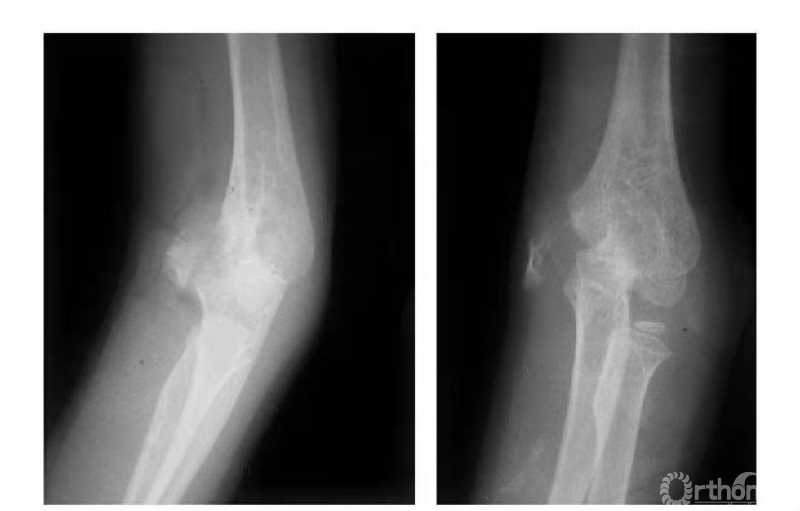

例3:肱骨内髁长斜形劈裂骨折(折线长约10cm)(图3)。

图3

例3:肱骨内髁骨折,骨块向前上移位,并上尺桡关节分离致尺肱关节不稳,且桡骨干近段呈代偿性粗大(图6)。

图6